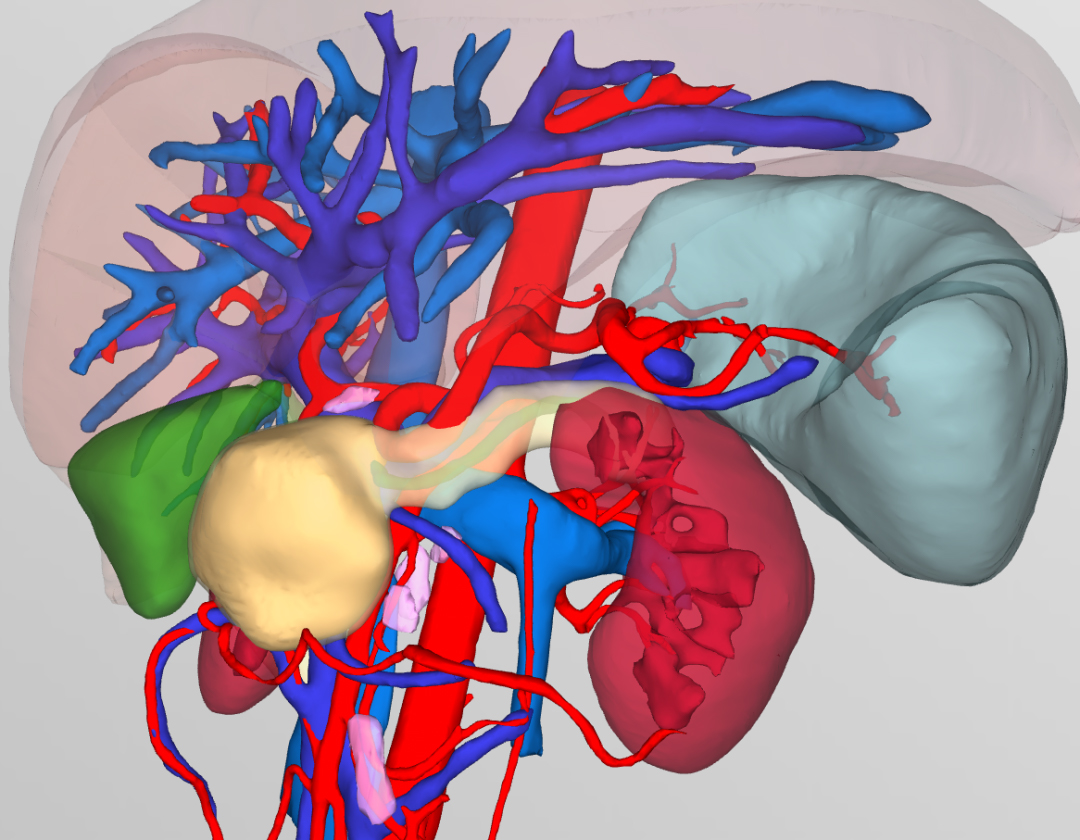

▲术前3D成像评估肿瘤情况(橙色部分为肿瘤)

▲术前3D成像评估肿瘤情况

(黄色部分为肿瘤)